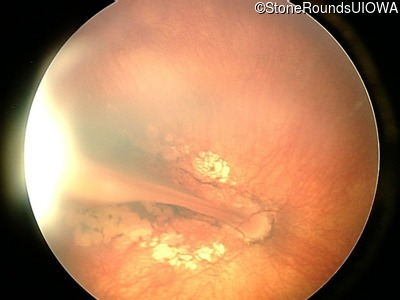

AD Familial Exudative Vitreoretinopathy (IIIE2b)

Age at visit: 23 months

OD OS

This 23 month old male has had nystagmus since shortly after birth. He was born at term (7lbs 12oz).